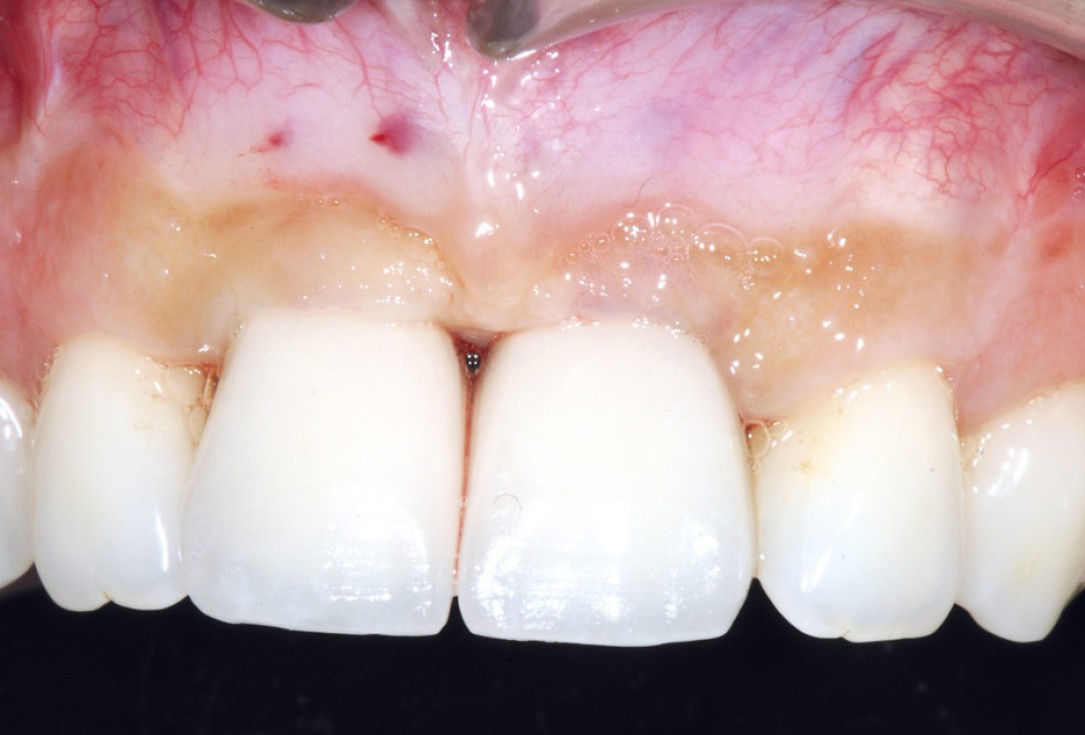

21/26 - 6 months after surgery: healthy soft tissuesBone augmentation in aesthetic zone with maxgraft® bonering - Dr. A. Patel

22/26 - Uncovering the implants 6 months after surgeryBone augmentation in aesthetic zone with maxgraft® bonering - Dr. A. Patel

25/26 - Final crowns immediatly after restorationBone augmentation in aesthetic zone with maxgraft® bonering - Dr. A. Patel